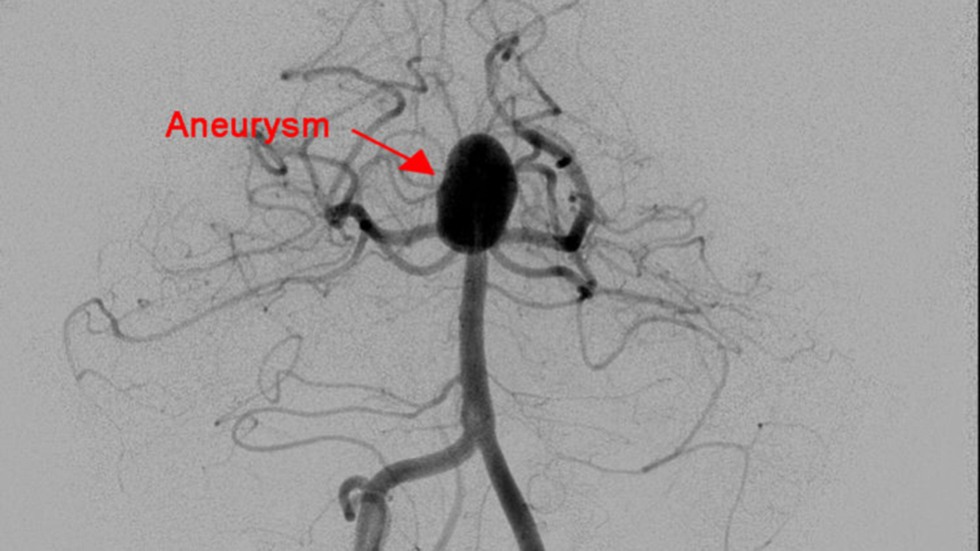

Primary Coil Embolization, Technique: Aneurysm

1 of 3

Primary Coil Embolization: Treats aneurysm from the inside rather than the outside. Fill aneurysm with embolic coils in order to obliterate blood flow.

Technique: Coil

2 of 3

Technique: Treated Aneurysm

3 of 3